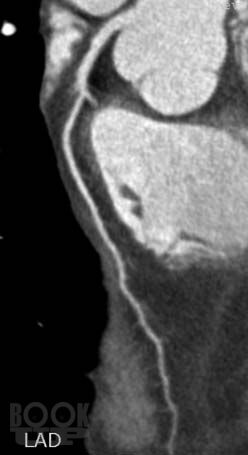

Достоинствами метода МСКТ-КГ являются неинвазивность и возможность оценить не только просвет коронарной артерии, проходимость аортокоронарных шунтов и стентов, но и состояние стенки сосуда, структуру атеросклеротической бляшки, а также возможность визуализации полостей сердца, миокарда и анатомических структур в зоне исследования.